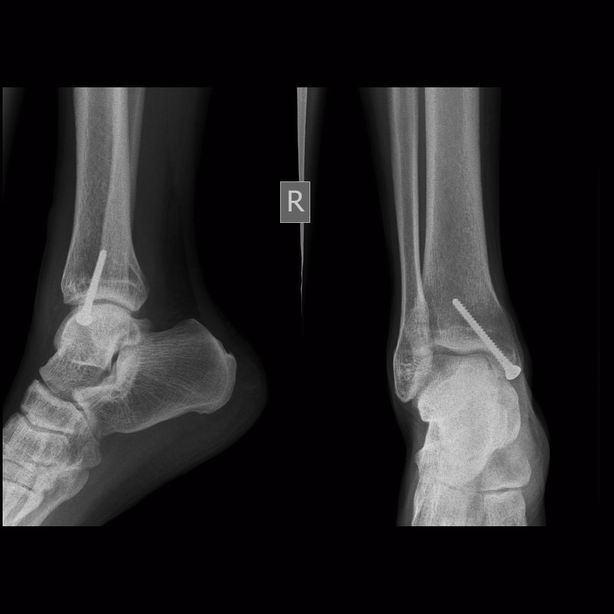

男,三十岁,多处外伤性骨折术后两月余。

骨化性肌炎:原因不明,多于外伤有关。好发于青年男性,多位于受伤部位的四肢深部组织如股四头肌、股内收肌、上臂肌及肘部肌群内,但不局限于肌肉。

临床上多有外伤史,及全身疾患如截瘫、昏迷等。早期局部肿胀、疼痛,可扪及包块,邻近关节活动受限。病理:早期为局部软组织水肿、变性、坏死、肌纤维断裂及原始间叶细胞增生形成肿块,之后肿块变硬,最外层形成成熟的纤维组织和骨组织,肿块不侵犯骨组织,但可与骨皮质相连。

影像表现为初期患处局限性肿胀,肌间隙模糊,密度增高,之后出现絮状钙化影及毛糙不整的网状致密影,邻近骨质可有骨膜反应;中期肿块内出现条状或层状钙化影,边缘部位出现致密骨。后期肿块缩小,与邻骨间以透亮带相隔或紧密相连,肿块内出现高密度钙化及骨结构形成,骨化影大部分沿肌束走行,是其重要鉴别点。需与下列疾病鉴别,1.骨外软组织骨肉瘤 2.骨外软骨肉瘤  3.皮质旁骨肉瘤 4.骨间膜钙化 5.进行性骨化性肌炎及软组织的其他钙化性疾病。

骨旁软组织内见广泛斑片条状密度增高影,考虑外伤性骨化性肌炎。